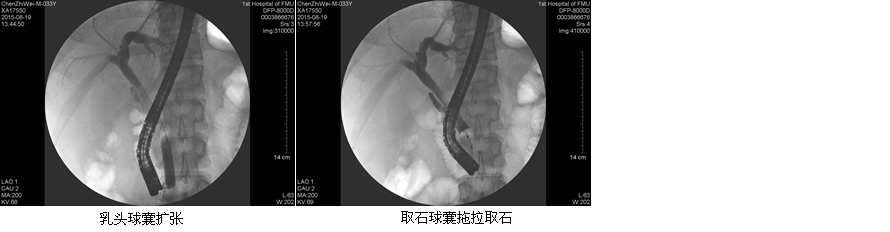

目前ERCP适应症主要包括:原因不明的阻塞性黄疸疑有肝外胆道梗阻者;疑有各种胆道疾病如结石、肿瘤、硬化性胆管炎等诊断不明者;疑有先天性胆道异常或胆囊术后症状再发者;胰腺疾病:胰腺肿瘤、慢性胰腺炎、胰腺囊肿等。在这50余例病例中,包含了内镜下乳头活检术、乳头括约肌切开取石术、胆管内支架引流术、鼻胆管引流术、“三镜”联合治疗胆总管结石等,患者术后无明显并发症发生,获得了良好的疗效,使我院ERCP诊疗技术进入一个崭新的时代。